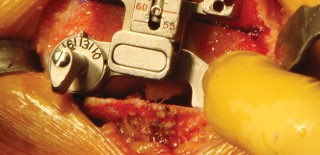

الخطوة 3: قطع عظم الساق (Tibial Cut)

- الدليل خارج النخاع (Extramedullary Guide): يُستخدم دليل خارج النخاع لقطع عظم الساق.

- إزالة الرباط الصليبي الأمامي (ACL): يتم قطع الرباط الصليبي الأمامي من موضع ارتباطه.

- تحريك الساق للأمام: تُحرك الساق للأمام (subluxed) لزيادة كشف الجزء العلوي من عظم الساق.

- وضع الدليل: يُوضع الدليل خارج النخاع فوق الثلث الإنسي من الحدبة الظنبوبية، بمحاذاة عرف الساق، وفي مركز مفصل الكاحل.

- تحديد الميل: يُحدد الميل المناسب ويُثبت الدليل في مكانه.

- القطع والحماية: تُحمى الأربطة الجانبية بالمبعدات، ويُقطع عظم الساق بشكل عمودي على محوره.

اعتبارات هامة (Pitfalls):

- يجب تجنب القطع المائل لعظم الساق (varus cut) بأي ثمن. يرتبط القطع المائل لعظم الساق في أي عملية استبدال مفصل الركبة بزيادة معدلات الفشل، خاصة في المرضى الذين يعانون من السمنة المفرطة. يحرص الأستاذ الدكتور محمد هطيف على الدقة القصوى لتجنب هذا الخطر.

الخطوة 4: إكمال قطع عظم الفخذ وتحديد الحجم

- نظام التوجيه الخلفي: يُستخدم نظام توجيه خلفي لإكمال قطع عظم الفخذ.

- تحديد الدوران الخارجي: يُحدد المقدار الصحيح للدوران الخارجي لعظم الفخذ بناءً على المحور اللقمي الخلفي، والمحور فوق اللقمتين، وزاوية 90 درجة بالنسبة لمحور الساق (السطح المقطوع)، والمحور الأمامي الخلفي (خط وايتسايد).

- تحديد الحجم: يُوضع الدليل على الجزء البعيد من عظم الفخذ، ويُحدد حجم عظم الفخذ، ويُختار الحجم المطابق للمريض.